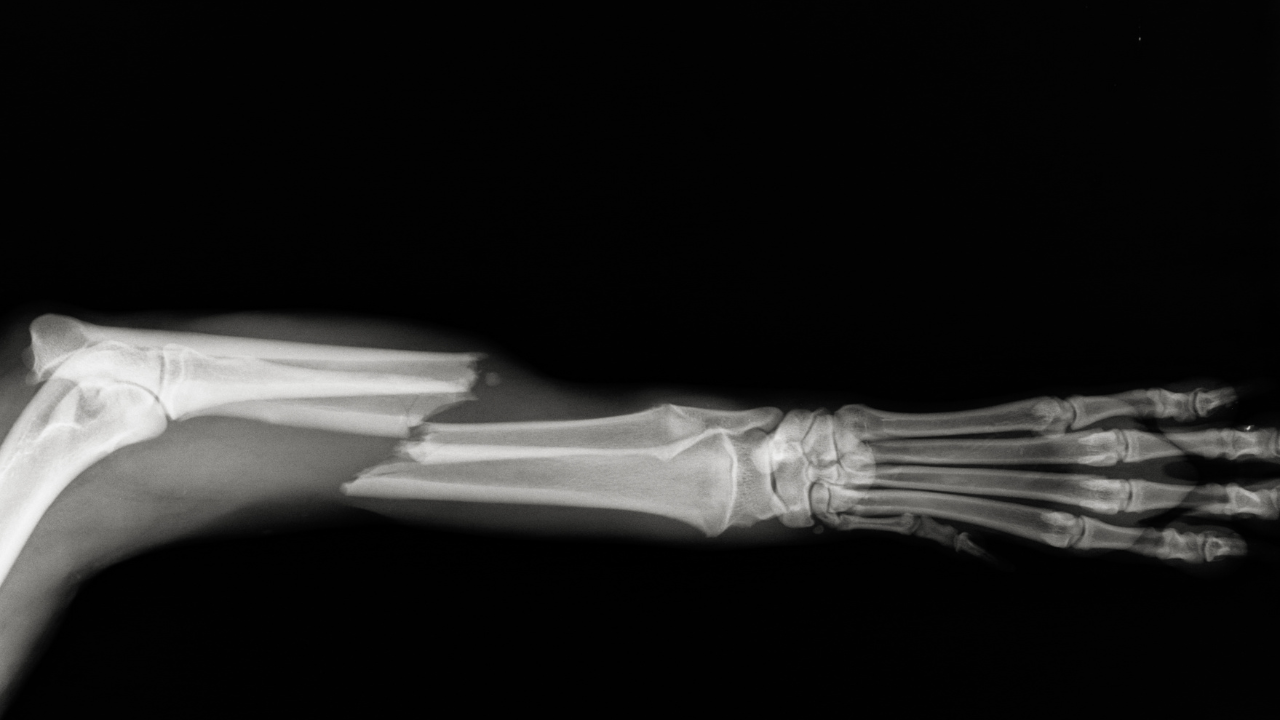

Managing wounds is often complicated, a marathon littered with infectious and inflammatory hurdles along the whole way. In this series, Drs. Goh and Marvel are our guides through the tensions of wound reconstruction and fracture repairs. We’ll start with a list of dressing options and opinions, recap bandaging foundations, and follow step-by-step flap tutorials. Then take a sharp turn into proper bone support using casts, splints, and surgery to achieve best results. This dynamic duo tag-teams the final lecture with real case examples, so you know what to do when they limp into your practice.

This five-video series tackles all kinds of wound care questions - when to consider coaptation, stabilizing fractures, and what to do when that wound won’t close. Be ready for the next “attacked by,” “hit by,” or “versus” case that calls in.